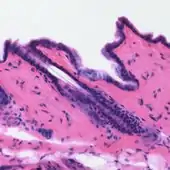

Haematoxylin stain is commonly followed (or counterstained) with another histologic stain, eosin.[10][11][1] When paired, this staining procedure is known as H&E staining, and is one of the most commonly used combinations in histology.[1][12][7][14] Haematoxylin is also a component of the Papanicolaou stain (or PAP stain) which is widely used in the study of cytology specimens, notably in the PAP test used to detect cervical cancer.[14][1]

Principally used as a nuclear stain (to stain the cell nucleus), haematoxylin will also stain rough endoplasmic reticulum, ribosomes, collagen, myelin, elastic fibers, and acid mucins.[10] Haematoxylin alone is not an effective stain, but when oxidized to hematein, and combined with a mordant, stains chromatin in cell nuclei dark blue to black.[1][7][25][10] The colour and specificity of haematoxylin stains are controlled by the chemical nature, and amount, of the mordant used, and the pH of the staining solution, thus, a variety of haematoxylin formulations have been developed.[1][10][15]